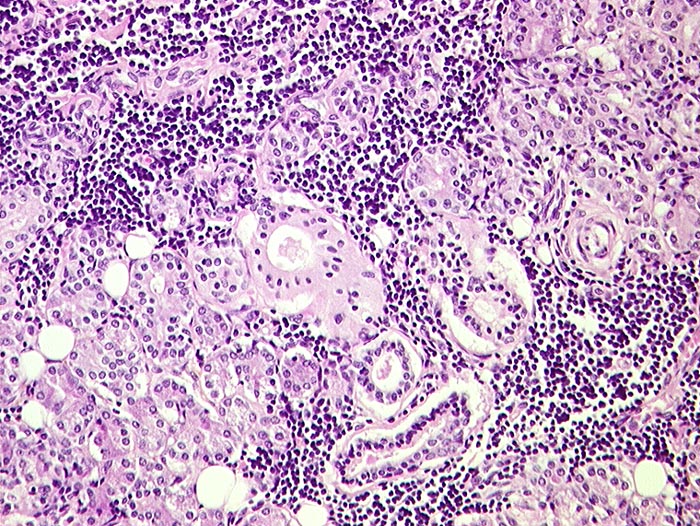

p/ Autoimmun- Sialadenitis bei Sjögren Syndrom

Autoimmun- Sialadenitis bei Sjögren Syndrom

Parotis

Das Zellbild ist je nach Stadium mehr oder weniger zellreich und zusammengesetzt aus Lymphozyten, Myoepithelien und selten Azinuszellen. Ein lymphozytäres Zellbild ist in Kombination mit dem typischen klinischen Bild (Keratokonjunktivitis sicca, Xerostomie, rheumatische Erkrankung) für die Sicherung der Diagnose ausreichend. Auf die Lippenbiopsie kann in diesem Fall verzichtet werden.